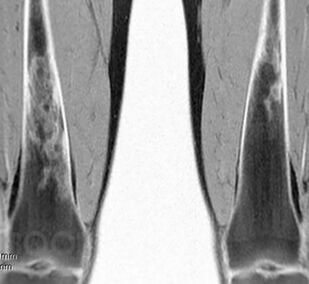

Болезнь Гоше относится к системным заболеваниям неопухолевой природы, в основе которых лежат наследственные дефекты метаболизма, приводящие к накоплению в органах и тканях нерасщепленных продуктов нормального обмена веществ. В случае болезни Гоше дефектом метаболизма является дефицит фермента, ответственного за метаболизм липидов.